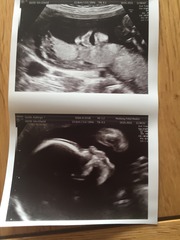

Afternnon ladies

Congrats Chook! Lovely pics :)

Lovely face shot of your baby chook.